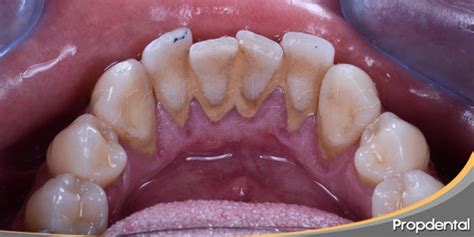

En un principio el sarro se formará de un color blanquecino, pero cuando va pasando el tiempo este se va poniendo amarillo y después marrón. A nadie le gusta tener los dientes con acumulaciones amarillentas, en especial porque afectarán en gran medida el estado estético de tu sonrisa.

El sarro se identifica fácilmente como una pasta amarillenta o marrón que se adhiere a nuestros dientes, pero es en realidad la calcificación de la placa dental. La placa se origina a través del contacto entre la saliva y las bacterias derivadas de los alimentos.

El color del sarro depende de la edad y de dónde aparece en la boca. El sarro sobre la línea de las encías, también denominado cálculo supragingival, es amarillo o tostado. El cálculo subgingival es el sarro que aparece debajo de la línea de las encías, el cual puede ser marrón, negro o verde.

La causa del sarro es la no eliminación de la placa bacteriana después de las comidas. Este pude acumularse fácilmente sobre los dientes, pero también entre ellos y las encías, por lo cual en ocasiones puede que no sea del todo visible. Por este motivo, lo más común es que aparezca en la parte trasera de los dientes delanteros inferiores que es una zona difícil de limpiar.